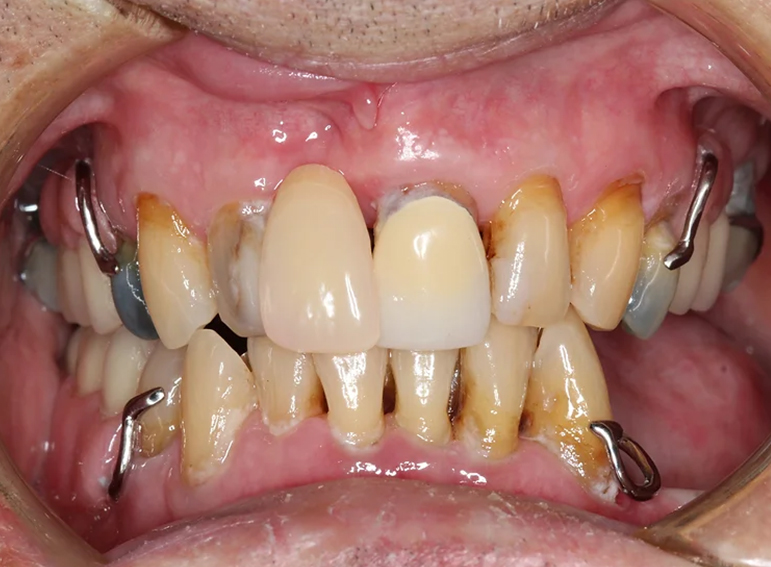

Complex upper and lower denture after oral cancer.